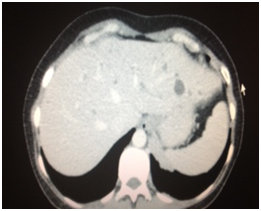

A subsequent CT Thorax/Abdomen/Pelvis (CT TAP) revealed a large mass encasing the left pulmonary artery with multiple lymph nodes and lesions on the liver (Figure 2). Further ultrasound indicated simple liver cysts (Figure 3). An ensuing Endobronchial ultrasound indicated squamous cell carcinoma with extensive necrosis; this finding was confirmed by bronchial washings. Finally, a PET CT disclosed uptake in the upper lobe with extensive mediastinal involvement, pleural metastasis, and chest wall invasion. There was no liver or bony involvement. The patient was not suitable for surgical treatment and was referred to the Medical Oncology team.

Figure 3 CT Abdomen showing cystic lesions on the liver.